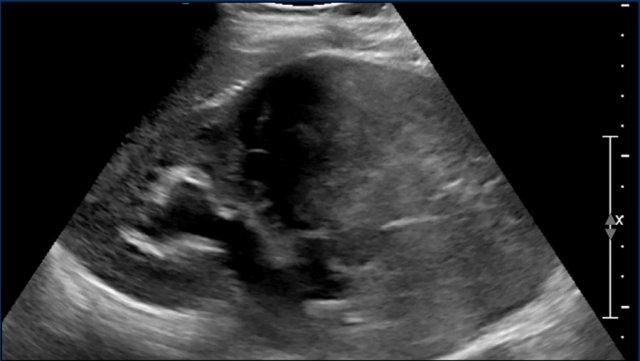

Video

Ở một bé trai sơ sinh, bác sĩ sản khoa sờ thấy một khối u ở bụng.

Siêu âm cho thấy một khối lớn ở cực trên thận phải. Đoạn video gợi ý hình ảnh xoáy cuộn ở một phần của khối u.

Tiếp tục với hình ảnh MRI.

MRI

Khối u có cường độ tín hiệu tương tự mô thận bình thường trên tất cả các chuỗi xung.

Mức độ ngấm thuốc tương phản từ của khối u cũng tương đương với phần nhu mô thận còn lại.

Thận đã được phẫu thuật cắt bỏ và kết quả giải phẫu bệnh xác nhận là u nguyên bào thận.